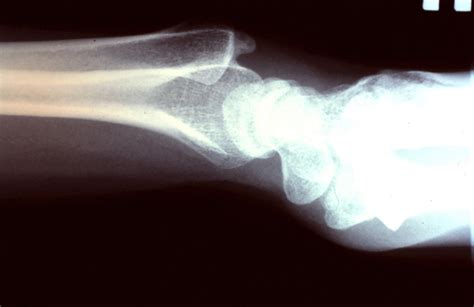

Syndactyly & Polydactyly: A Guide to Hand Anomalies Hey guys, ever wondered about those unique hand conditions like fingers being joined together or having an extra digit? Today, we’re diving deep into two fascinating, yet often misunderstood, congenital hand anomalies: Syndactyly and Polydactyly . These conditions, while sounding complex, are simply variations in hand development that occur before birth. Understanding them is key, not just for medical professionals but for anyone interested in the amazing diversity of human anatomy and the incredible progress in pediatric reconstructive surgery. We’re going to break down what syndactyly polidaktili adalah (what syndactyly and polydactyly are) in a way that’s easy to grasp, focusing on causes, types, diagnosis, and the journey of treatment and recovery. So, let’s explore these conditions and shed some light on what it’s like to navigate them. ## What Exactly is Syndactyly? Understanding Fused Fingers Let’s kick things off by really understanding syndactyly . Simply put, syndactyly is a condition where two or more fingers (or toes, though we’ll focus on hands here) are fused together . Imagine, guys, a baby being born and their digits aren’t quite separated; they’re joined, often by skin, but sometimes by bone. This isn’t just a minor cosmetic issue; depending on the severity, it can significantly impact hand function. The term itself comes from Greek: ‘syn’ meaning together , and ‘dactylos’ meaning finger . It’s one of the most common congenital hand differences, affecting approximately 1 in every 2,000 to 2,500 live births. It can be found in isolation, meaning it’s the only birth difference present, or it can be part of a broader genetic syndrome, like Apert syndrome or Poland syndrome, which makes understanding its cause even more crucial for families. When we talk about syndactyly , it’s not a one-size-fits-all situation. There are different classifications that help medical teams understand the specific presentation and plan the best course of action. Firstly, there’s cutaneous syndactyly , where only the skin and soft tissues are joined. Think of it like a web between the fingers. Then, we have the more complex osseous syndactyly , where the bones of the fingers are actually fused together, making the separation process more intricate. Beyond that, the fusion can be complete , extending all the way from the base to the tip of the fingers, or incomplete , meaning only a portion of the fingers are joined. For example, you might see webbing only at the base of the fingers. The specific fingers involved also vary; the middle and ring fingers are most commonly affected, but any combination is possible. It can occur on one hand (unilateral) or both hands (bilateral), further adding to the unique presentation of each case. So, what causes syndactyly ? Well, a lot of the time, it’s considered sporadic, meaning it occurs randomly with no clear genetic link or family history. However, genetics definitely play a role in a good number of cases. It’s thought to happen when the normal process of programmed cell death (apoptosis) during fetal development, which is responsible for separating the fingers, doesn’t quite complete its job. This typically occurs between the sixth and eighth weeks of gestation. If there’s a family history of syndactyly, there’s an increased chance of it appearing in subsequent generations, often following an autosomal dominant inheritance pattern . Environmental factors are less commonly implicated, but researchers are always studying potential links. The diagnosis is usually quite straightforward, often made at birth, as the fused digits are visually apparent. Sometimes, it might be suspected during a prenatal ultrasound, allowing families to prepare and gather information even before the baby arrives. Early diagnosis is super important, guys, because it allows for timely consultation with specialists, typically a pediatric hand surgeon, to discuss potential treatment pathways. Understanding these nuances of syndactyly is the first step in supporting individuals affected by it and ensuring they receive the best care possible. It’s all about giving these kids the best shot at full hand function and a positive self-image, empowering them through thoughtful medical intervention. ## Diving Deep into Polydactyly: Exploring Extra Digits Alright, guys, now let’s shift gears and talk about its cousin, polydactyly . While syndactyly is about fused fingers, polydactyly is literally the opposite – it’s about having extra digits! The term itself is derived from Greek, with ‘poly’ meaning many and ‘dactylos’ meaning finger . So, if you hear someone talking about polydactyly , they’re referring to someone being born with more than the usual five fingers on a hand (or five toes on a foot). It’s also a surprisingly common congenital hand anomaly, even more so than syndactyly in some populations, with estimates suggesting it affects about 1 in every 500 to 1,000 live births. Just like syndactyly, polydactyly can be an isolated finding, or it can be a feature of a more complex genetic syndrome, such as Ellis-van Creveld syndrome or Bardet-Biedl syndrome. The extra digit, often called a supernumerary digit, can range from a tiny, underdeveloped nub of soft tissue to a fully formed, functional finger complete with bones, joints, and even nails. Now, polydactyly isn’t just one thing; there are several types, classified based on where the extra digit appears on the hand. This classification is crucial for guiding treatment. The most common type is postaxial polydactyly , which means the extra digit appears on the ulnar side of the hand, outside the little finger. Think of it as an extra pinky finger. This is particularly common in individuals of African descent and often runs in families. Next, we have preaxial polydactyly , where the extra digit appears on the radial side of the hand, near the thumb. This means an extra thumb, which can vary greatly in its development, from a small skin tag to a duplicate thumb. This type is more common in Asian populations and Caucasian populations, and it often has a stronger genetic component. Finally, there’s central polydactyly , which is much rarer and involves an extra digit appearing between the existing fingers, typically the ring, middle, or index fingers. Understanding these distinctions helps surgeons determine the best approach for removal or reconstruction. So, what causes polydactyly ? Similar to syndactyly, it’s believed to stem from issues during embryonic development, specifically when the hand plate is forming. Instead of the limb bud developing into five distinct rays (fingers), an additional ray forms. This usually happens around the fifth to eighth week of pregnancy. Many cases of polydactyly, especially postaxial, are autosomal dominant , meaning if one parent has it, there’s a 50% chance each child will inherit it. However, like syndactyly, it can also occur sporadically without any known family history. Environmental factors are rarely identified as primary causes. The diagnosis of polydactyly is almost always made at birth because the extra digit is visibly obvious. Occasionally, it might be picked up on a prenatal ultrasound, providing families with advanced notice. Early consultation with a pediatric hand specialist is essential. They can assess the structure of the extra digit, often using X-rays to see the underlying bone structure, and discuss the best timing and method for removal or reconstruction. The goal for treatment, guys, is not just cosmetic; it’s also about improving hand function, preventing potential difficulties with gripping or fine motor skills, and addressing any discomfort, ensuring the child can use their hand confidently and effectively. It’s all about empowering these kids for a lifetime of activity. ## Are They Related? Understanding the Connection (or Lack Thereof) Now that we’ve really gotten into the nitty-gritty of syndactyly and polydactyly individually, a common question pops up: Are syndactyly and polydactyly related ? Do they often appear together, or are they completely distinct conditions? Well, guys, it’s a bit of both, but generally, they are considered separate congenital anomalies, each with its own developmental pathways and genetic predispositions. While it’s certainly possible for a person to have both syndactyly and polydactyly, it’s not the norm for them to occur simultaneously in the same hand as a single, combined defect. When they do co-exist, it often points to a more complex underlying genetic syndrome rather than a random coincidence. Let’s break down the typical scenario. Most cases of isolated syndactyly (where only fused fingers are present) or isolated polydactyly (where only extra fingers are present) occur independently. Their developmental origins, though both stemming from issues during the formation of the limb bud in early pregnancy, involve different cellular processes. Syndactyly results from a failure of separation – the programmed cell death that usually carves out individual fingers doesn’t happen completely. Polydactyly, on the other hand, results from an overformation or duplication of tissue – an extra ray forms during limb development. These are fundamentally different mechanisms, which is why seeing them together without other systemic findings is relatively rare. However, and this is where it gets interesting, both conditions can be features of various genetic syndromes. This is where the connection truly lies. For example, conditions like Bardet-Biedl syndrome, which is a rare genetic disorder affecting multiple organ systems, can present with both polydactyly and syndactyly. Similarly, certain forms of chondroectodermal dysplasia (Ellis-van Creveld syndrome) can involve a combination of both conditions, alongside other skeletal and heart anomalies. When a child presents with both syndactyly and polydactyly , especially if there are other unusual features or medical concerns, it’s a strong indicator for genetic testing and a thorough evaluation by a geneticist. This helps identify any underlying syndrome, which is crucial for comprehensive management, as these syndromes often have implications for other organ systems beyond just the hands. It’s important for families and medical professionals to understand this distinction. If a child has isolated syndactyly, the focus is primarily on surgical correction of the fused digits. If they have isolated polydactyly, the focus is on the removal or reconstruction of the extra digit. But if both syndactyly and polydactyly are present, or if either condition is accompanied by other physical findings, the diagnostic pathway expands significantly. It’s no longer just about the hand anomaly itself, but about understanding the broader picture of the child’s health and potential needs. So, while they are distinct conditions developmentally, their occasional co-occurrence often serves as a valuable clinical clue, guiding further investigation into an underlying genetic cause. This comprehensive approach ensures that individuals receive holistic care, addressing not just the visible hand differences but any associated health challenges, providing the best possible support for their overall well-being. It really highlights how interconnected our bodies are and the importance of looking at the whole person, not just isolated symptoms, when it comes to congenital anomalies. ## Navigating the Journey: Diagnosis, Treatment, and Support For families embarking on the journey of syndactyly and polydactyly , understanding the path from diagnosis to treatment and beyond is absolutely crucial. This isn’t just about a medical procedure, guys; it’s about a child’s future function, self-esteem, and overall well-being. The first step, as we’ve discussed, is usually diagnosis . Most often, both syndactyly and polydactyly are identified at birth during the newborn examination. The pediatrician will visually inspect the baby’s hands and feet. In some cases, if the anomalies are prominent, they might even be detected during prenatal ultrasound scans, giving parents precious time to learn about the condition, connect with specialists, and prepare emotionally. Once a diagnosis is made, the next step is typically a referral to a pediatric hand surgeon or an orthopedic surgeon specializing in congenital hand differences. This specialist will conduct a thorough physical examination and often order X-rays to understand the underlying bone structure – whether bones are fused in syndactyly, or if the extra digit in polydactyly contains bone, cartilage, or just soft tissue. This detailed imaging is vital for planning the surgical approach. Now, let’s talk about treatment , which is primarily surgical for both conditions. For syndactyly , the goal of surgery is to separate the fused fingers, creating distinct, functional digits. The timing of surgery is often critical. Generally, simple cutaneous syndactyly (skin only) between the fingers might be corrected around 6 months to 1 year of age. More complex cases, especially those involving the thumb or multiple digits, might be addressed earlier or require staged surgeries. The surgeon carefully incises the skin along the planned separation line, often using zigzag incisions to prevent linear scarring and contractures. Skin grafts, usually taken from the groin or arm, are frequently necessary to cover the newly created raw surfaces between the fingers. This prevents the fingers from fusing back together and ensures good range of motion. Post-operatively, a cast or splint is worn for several weeks, followed by hand therapy to maximize function and minimize stiffness. For polydactyly , the treatment also involves surgery, but the approach varies significantly based on the type and complexity of the extra digit. For a small, underdeveloped postaxial extra digit (like an extra pinky that’s mostly soft tissue), a simple ligation (tying off) procedure may be performed shortly after birth. This cuts off the blood supply, causing the digit to shrivel and fall off. However, if the extra digit has bone, cartilage, or is more developed, surgical excision is required, typically performed between 6 months and 1 year of age. The surgeon carefully removes the extra digit, often reconstructing the remaining digit(s) to ensure proper alignment and function. For preaxial polydactyly (extra thumb), the surgery is often more complex, aiming to create one functional, well-aligned thumb from the duplicated structures, which might involve fusing bones or reconstructing ligaments. Just like with syndactyly, post-operative care includes splinting and often hand therapy to ensure the best possible outcome. Beyond the surgery itself, support for the child and family is paramount. This includes emotional support, genetic counseling (especially if a syndrome is suspected), and ongoing physical and occupational therapy. Therapists play a crucial role in helping the child regain strength, flexibility, and fine motor skills after surgery. Family support groups can also be incredibly valuable, offering a space to share experiences and advice. Early intervention in both diagnosis and treatment, combined with comprehensive support, significantly improves outcomes, allowing these children to live full, active lives with functional hands. Remember, guys, this journey is about empowering the child, giving them the best tools for their development, and celebrating their unique strengths. ## Living with Syndactyly and Polydactyly: A Positive Outlook Living with or having undergone treatment for syndactyly and polydactyly is a testament to resilience, adaptability, and the incredible progress in modern medicine. For families and individuals, it’s not just about overcoming a physical challenge; it’s about embracing uniqueness and fostering a positive outlook. In the past, these conditions might have carried a stigma, but today, with advanced surgical techniques and a more inclusive societal view, children and adults with corrected (or even uncorrected) hand differences can lead incredibly fulfilling lives. This positive shift is a huge deal, guys, and it’s something worth celebrating. The focus in modern pediatric hand surgery is always on maximizing function first and foremost. While cosmetic results are important for self-esteem, the primary goal is to ensure the hand works as effectively as possible – allowing children to grasp objects, write, play sports, and engage in all the activities that define childhood and beyond. Thanks to skilled surgeons, many children who undergo corrective surgery for syndactyly achieve excellent functional outcomes. Their separated fingers move independently, allowing for a wide range of motion and dexterity. Similarly, for those with polydactyly , the removal of the extra digit (or reconstruction of the thumb) often results in a hand that looks and functions very close to typical, allowing for confident use in daily tasks. The success stories are truly inspiring, showcasing kids who climb, paint, play instruments, and excel in sports, all thanks to meticulous surgical planning and dedicated rehabilitation. However, the journey doesn’t always end with surgery. Ongoing care might include periodic check-ups with the hand surgeon, continued physical or occupational therapy to address any residual stiffness or strength issues, and sometimes, psychological support for children as they grow and navigate self-image. It’s okay to acknowledge that sometimes, there are emotional aspects to having a visible difference, even after successful correction. This is where the power of community and support groups comes in. Connecting with other families who have gone through similar experiences can provide invaluable comfort, practical advice, and a sense of belonging. Online forums, local meet-ups, and dedicated organizations offer platforms for sharing stories, challenges, and triumphs. These networks reinforce the message that no one is alone in this journey. Moreover, advancements in medical technology are continuously improving outcomes. Innovations in microsurgery, imaging, and rehabilitation protocols mean that today’s children receive care that is more precise and effective than ever before. Researchers are also delving deeper into the genetics of these conditions, hoping to unlock even more insights into prevention and novel treatments. The future for individuals with syndactyly and polydactyly is bright, full of possibilities. It’s a powerful reminder that while our bodies may present in unique ways, with the right medical care, support, and a can-do attitude, every individual has the potential to thrive and contribute their unique talents to the world. It’s about celebrating what makes each of us special and ensuring everyone has the opportunity to reach their full potential, regardless of their starting point. So, there you have it, guys – a comprehensive look at syndactyly and polydactyly . We’ve explored what these conditions are, from fused fingers to extra digits, delved into their distinct types and causes, and understood how genetics and developmental biology play their roles. We’ve also walked through the critical steps of diagnosis, the intricacies of surgical treatment, and the indispensable role of post-operative support and therapy. These aren’t just medical terms; they represent unique journeys for individuals and their families. The key takeaway here is that while congenital hand anomalies can present challenges, modern medicine, coupled with incredible human resilience and strong support systems, empowers individuals to achieve excellent functional and cosmetic outcomes. If you or someone you know is navigating this path, remember that knowledge is power, early intervention is key, and a positive, supportive community can make all the difference. Embrace the uniqueness, seek the best care, and always look forward to a future filled with possibility.